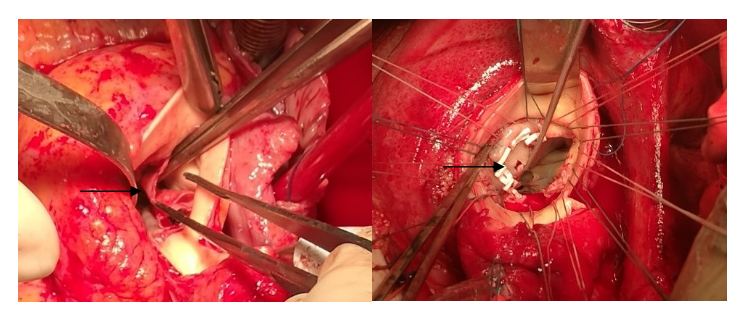

该研究提出了一种创新的手术技术:对于左心室流出道感染残腔形成或处于感染急性期的患者,在重建的主动脉瓣环左心室侧生物补片上打孔(4.0mm)。这一技术可有效减少湍流和血流停滞,从而预防脓肿形成,并增强局部抗生素治疗的疗效(如图1)。

图1. 生物补片重建主动脉瓣环后左室流出道打孔(4.0mm)

研究回顾性分析了2017年10月至2022年12月期间21例因感染性心内膜炎(IE)累及主动脉瓣环的患者。所有患者均在低温体外循环下接受了心脏手术,包括瓣膜置换和瓣环重建。其中,16例患者进行了瓣环重建,8例因LVOT残留腔在左心室侧打孔。结果显示,所有患者术后存活,心功能显著改善,无死亡或严重并发症。随访期间,未出现瓣周漏、脓肿或感染复发。